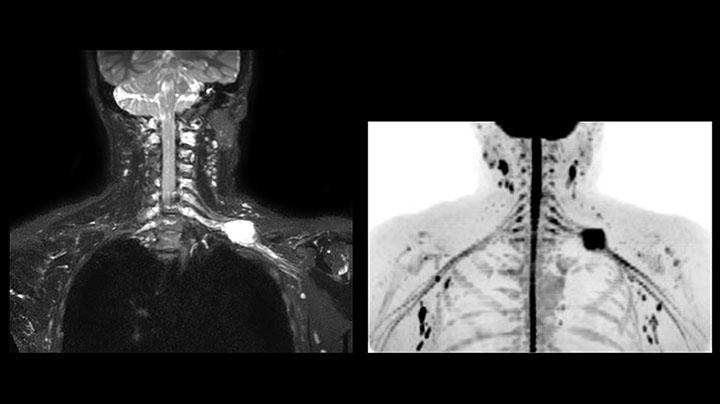

Hier handelt es sich um eine 43-jährige Patientin mit einem supraklavikulären Nervenscheidentumor links. Die Läsion ist auf den STIR VISTA Bildern und auf der MR-Neurographie mit diffusionsgewichteter MRT gut zu erkennen. Die Untersuchung wurde mit Prodiva 1.5T durchgeführt.

Erfasste Voxelgröße: 1,2 x 1,3 x 2,4 mm, rekonstruierte Voxelgröße: 0,7 x 0,7 x 1,2 mm, dS SENSE Faktor: 2, Scandauer: 5:46 Minuten.